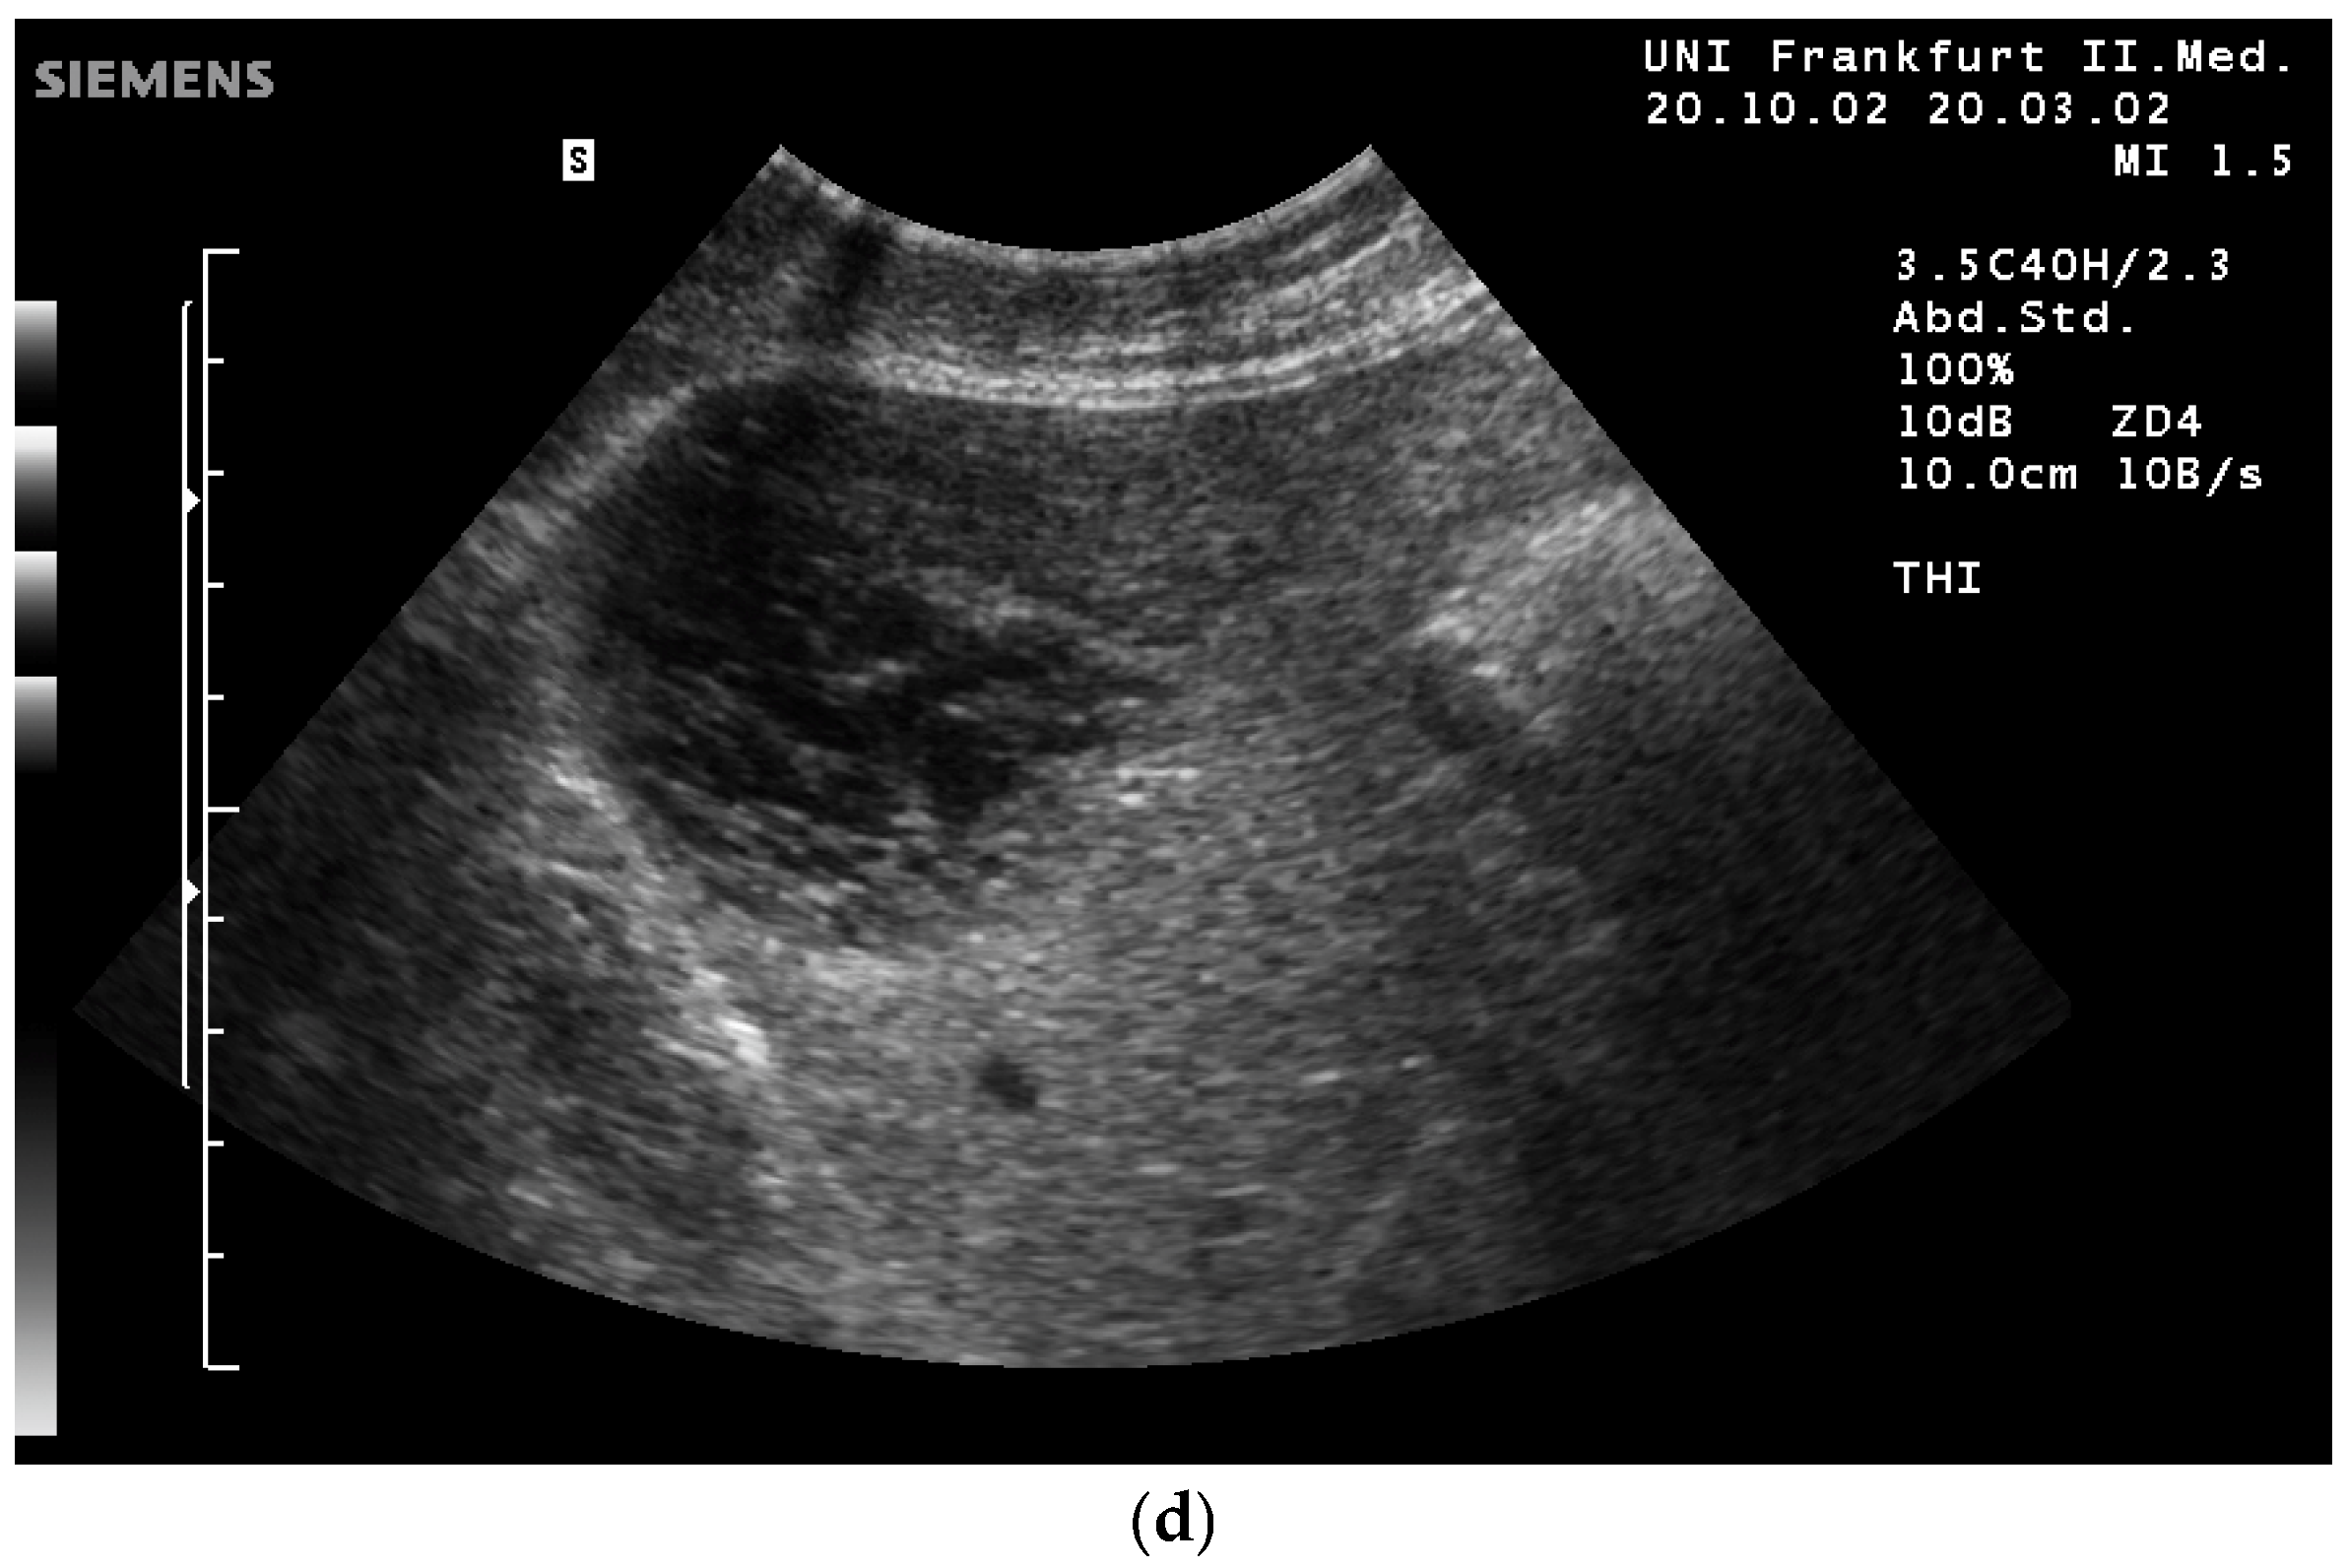

- Fischer, T.; Filimonow, S.; Taupitz, M.; Petersein, J.; Beyersdorff, D.; Bollow, M.; Hamm, B. [Image quality and detection of pathology by ultrasound: Comparison of B-mode ultrasound with photopic imaging and tissue harmonic imaging alone and in combination]. Rofo 2002, 174, 1313–1317. [Google Scholar] [CrossRef] [PubMed]

- Can be used together with THI